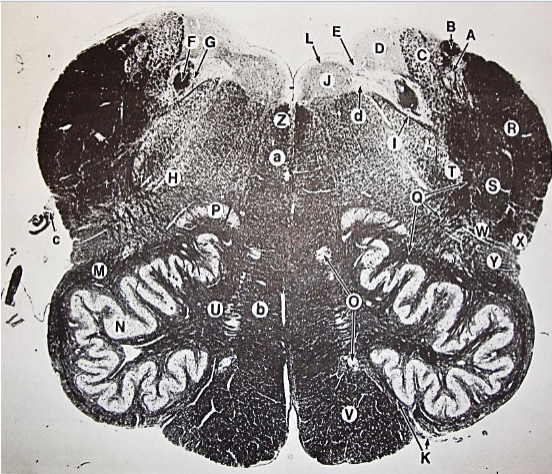

A

posterior median sulcus

B

posterior intermediate sulcus

C

anterior median fissure

D

gracile fasciculus

E

Gracile nucleus

F

fasciculus cuneatus

G

spinal trigeminal tract

H+I collectively

spinal trigeminal nucleus

J

Accessory nucleus

K

pyramidal decussation

L

lateral corticospinal tract

M

rubrospinal tract

N

posterior spinocerebellar tract

O

anterior spinocerebellar tract

P

lateral spinothalamic tract

Q

anterior spinothalamic tract

R

lateral vestibulospinal tract

S

medial longitudinal fasciculus

T

tectospinal tract

U

central canal